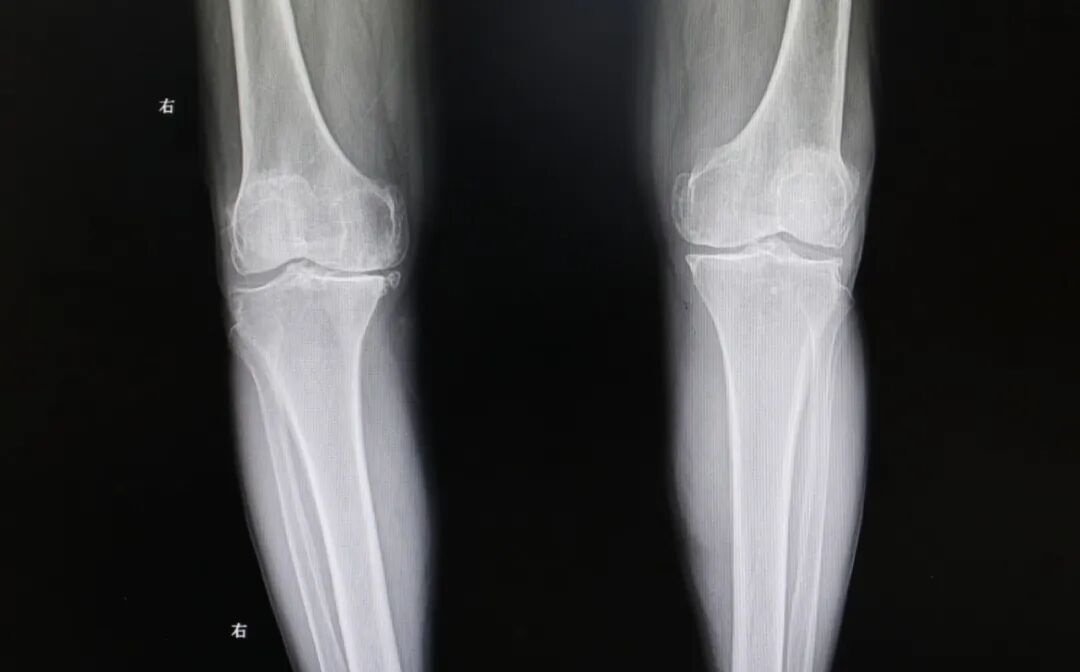

膝盖为啥一凉就“摆烂” 脆皮预警:膝盖,作为全身最复杂、承重最大的关节之一,其实是个“皮薄馅大”的结构。表面肌肉脂肪覆盖少,对温度变化极其敏感。当冷空气来袭关节周围的血管会条件反射般收缩,导致血液循环速度减缓。血流一慢,关节滑液(天然的润滑剂)分泌减少,运走代谢废物(如炎性因子)的速度就变慢。同时,关节内的滑膜和神经末梢对寒冷刺激异常敏感,僵硬、酸胀和疼痛感就会被放大。 疼痛不一定是风湿、类风湿 风湿背锅:“我这是不是风湿?”几乎是所有膝盖受凉疼痛者的第一疑问。医学上的风湿免疫性疾病,如类风湿关节炎、强直性脊柱炎等,是自身免疫系统攻击自身组织导致的严重疾病,必须有明确的免疫指标异常和关节破坏证据。 刘主任表示:“父母说的“老寒腿”或“风湿”,在医生眼里,更准确的描述是“膝关节退行性变”或“骨关节炎”的早期表现,属于关节的磨损、老化,和免疫系统紊乱无关。”下次膝盖疼,别再简单归咎于“风湿”了。分清这一点,才能从盲目的担忧,转向正确的保养和就医方向。 什么才是真“风湿” 危险信号:既然普通受凉疼不是真风湿,那什么症状才需要拉响警报,是真正的风湿病呢?记住以下几个关键词: 对称性疼痛 真正的风湿性关节炎(如类风湿)很少只盯着一个膝盖不放。它通常对称性地侵犯双手腕、手指关节、脚趾等小关节。如果你的疼痛是“双膝+双手”组合,就要警惕。 晨僵 早上起床后,关节僵硬得像生了锈,活动超过30分钟甚至1小时才能缓解,这是典型的炎症性“晨僵”,是风湿病的重要标志。单纯受凉的酸痛,活动几下反而会好转。 全身性不适 身体会发出其他信号:不明原因的长期低热、乏力、体重下降,或者出现皮疹(如脸颊蝶形红斑)、反复口腔溃疡、口干眼干、脱发等。 休息的时候也痛 关节在静止、休息时疼痛更明显,适当活动后减轻,这与劳损性疼痛(活动后加重)相反。 如果“膝盖疼”仅仅是受凉诱发、保暖缓解、位置固定、没有全身症状,那么它属于劳损或退变的范畴远大于风湿病。了解这些区别,能避免不必要的焦虑。 什么时候需要找医生 疼痛性质改变:从“受凉才疼”变成持续疼、夜间静息痛。 功能出现障碍:膝盖突然卡住动不了、打软腿差点跪下,或关节明显肿胀、发热、变形。 居家养护无效:严格保暖休息超过1周,疼痛毫无缓解。 近期一位60多岁的老人,他就是典型的风湿关节炎,膝盖遇冷就疼,起初没当回事,就是贴敷膏药,十多年就这样间歇疼,最近一年疼痛明显加剧,上下楼梯困难,尤其是早上起床后麻木僵硬,这才让孩子们带着来到我院。 刘海亮主任仔细为老人检查,发现他已是终末期风湿性关节炎,保守治疗已经起不到任何效果,针对这类情况,通常考虑进行膝关节置换手术,可有效解决膝关节磨损、矫正变形,并消除患者的疼痛。 完善术前准备,老人的膝关节置换手术成功完成,老人的新生活也即将开始。 术后第二天老人即可下地,及时有效的康复锻炼可以达到快速康复的效果。